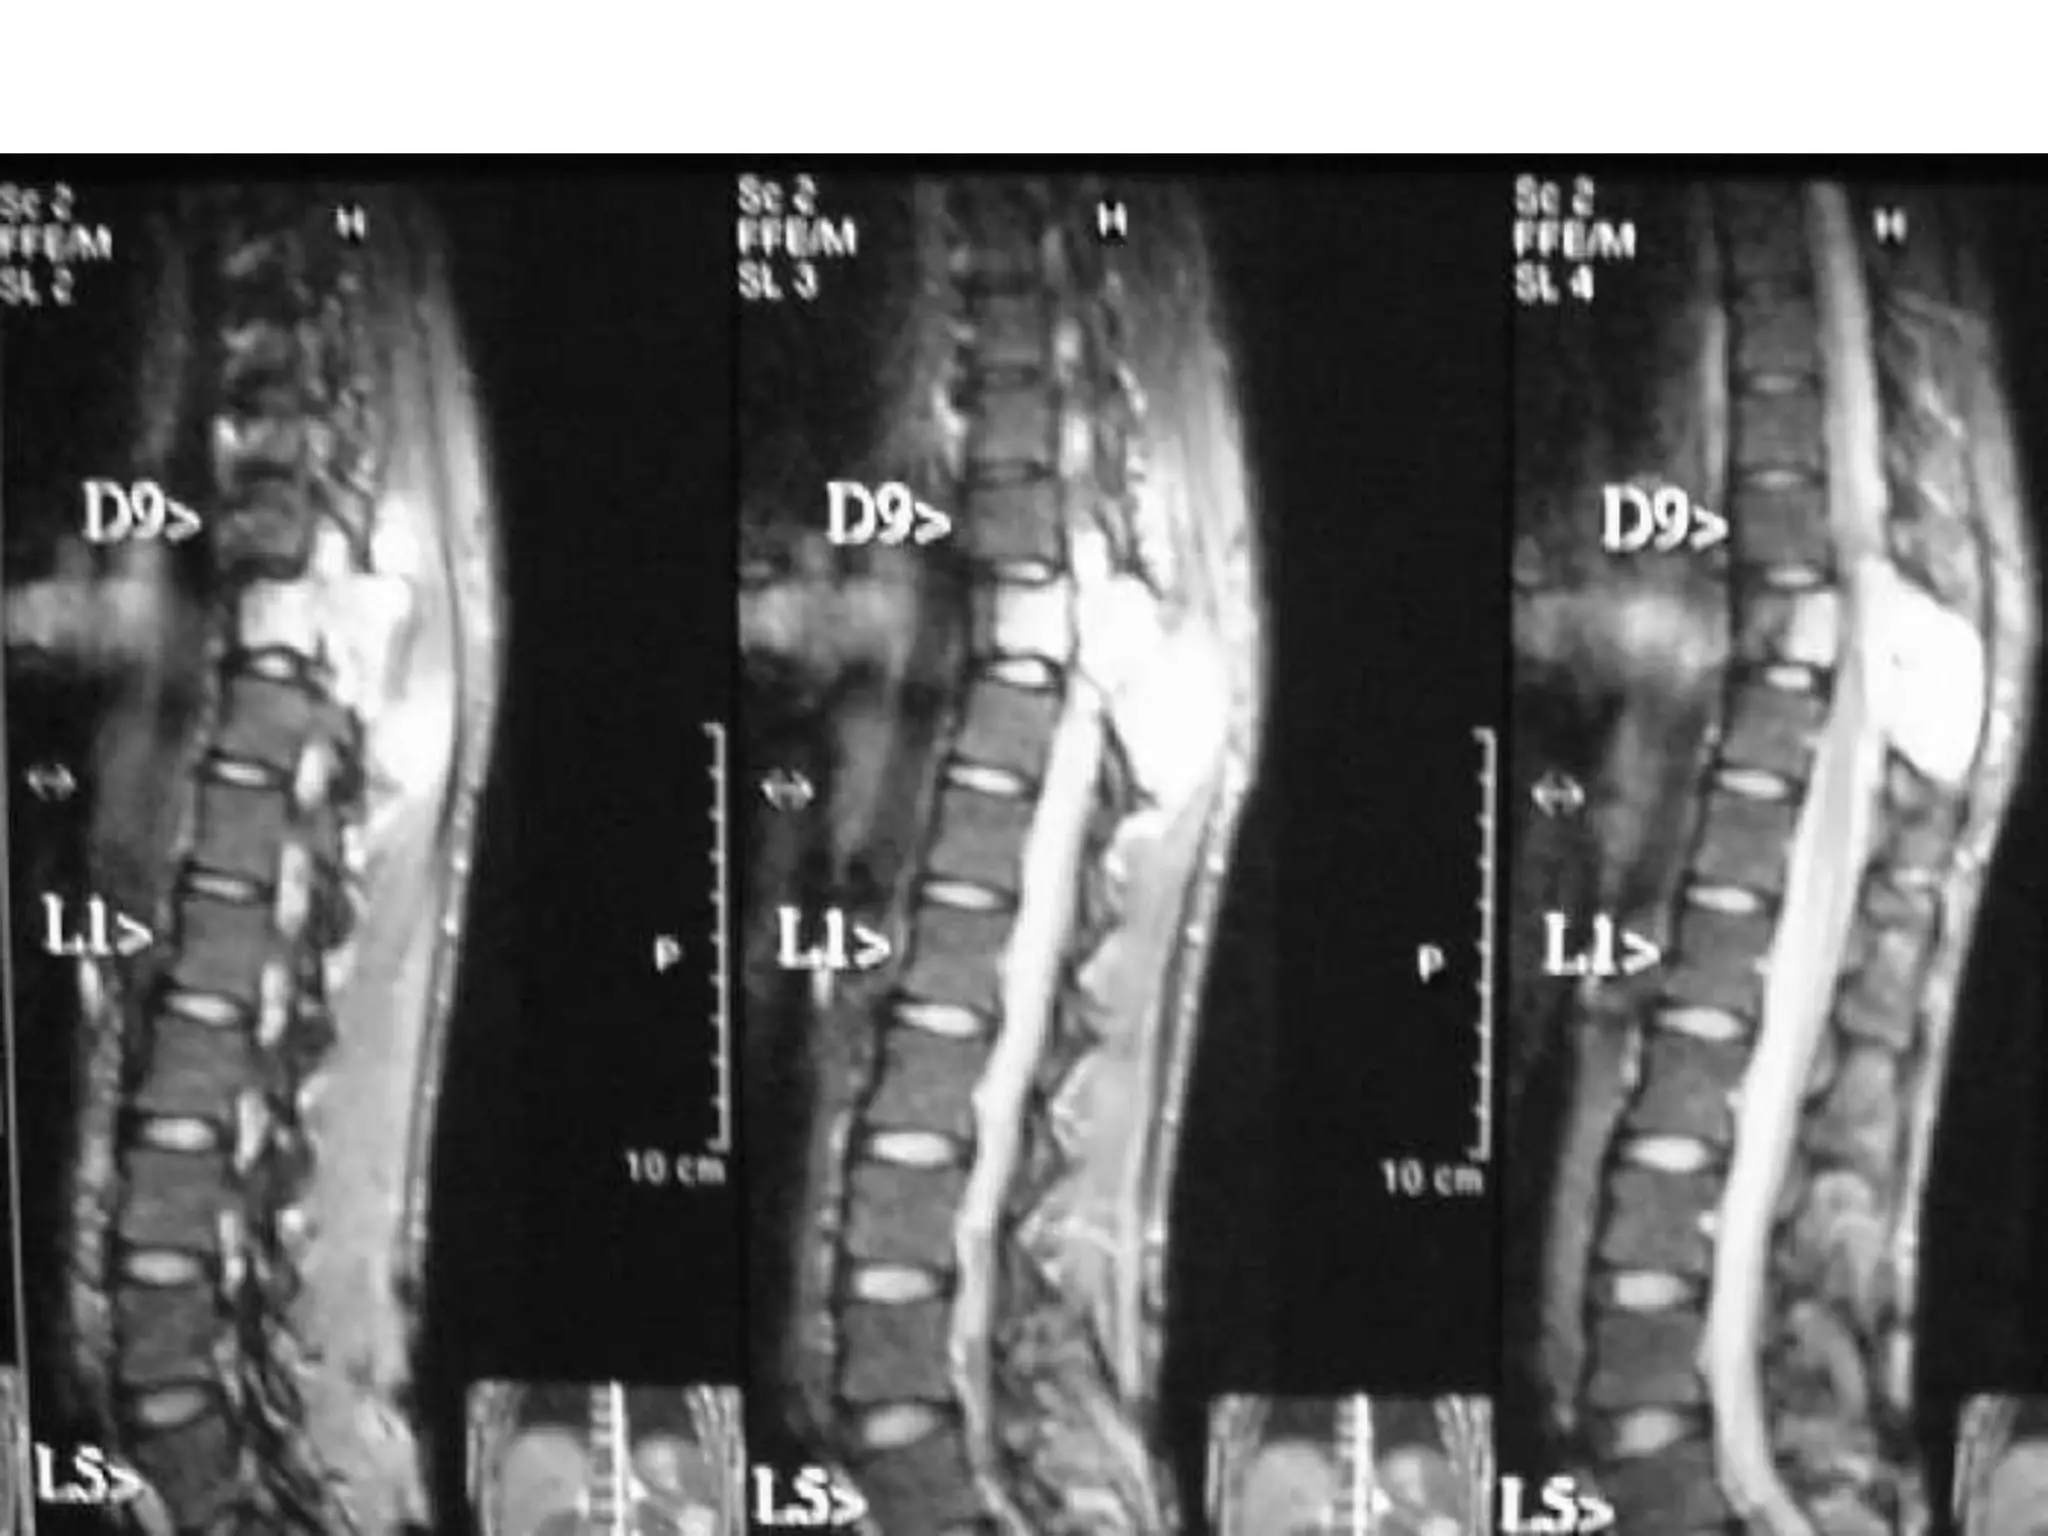

AV malformation